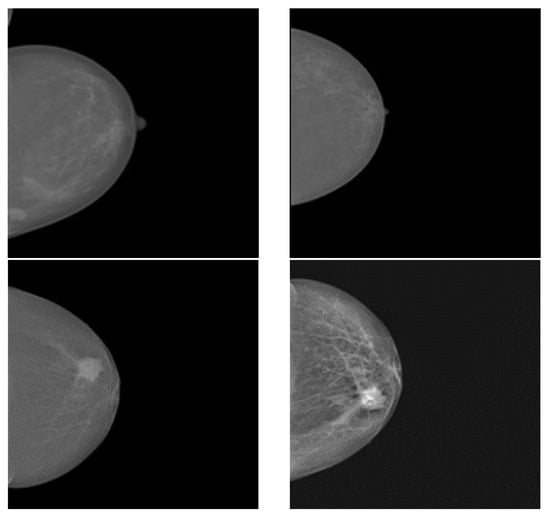

2.1. Dataset